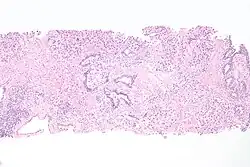

Histopathology of urothelial carcinoma of the urinary bladder, showing a nested pattern of invasion. Transurethral biopsy. H&E stain -

Histopathology of urothelial carcinoma of the urinary bladder. -